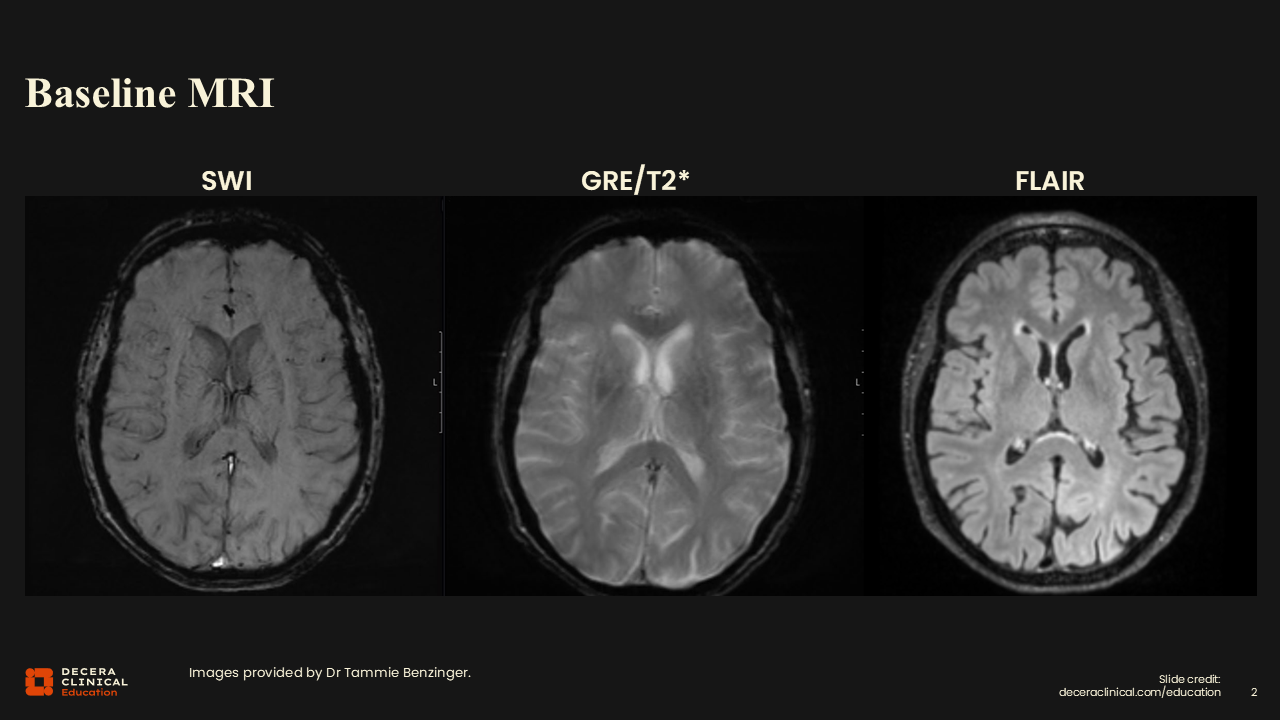

Case 1: Eligibility and Baseline Assessment

In this case, an 83-year-old woman presented with memory loss. She lived alone in a freestanding house and remained independent in activities of daily living (ADLs), including cooking, shopping, and laundry. Her Mini-Mental State Exam (MMSE) score was 27/30, and her Clinical Dementia Rating (CDR) was 0.5, both of which indicate questionable to very mild cognitive impairment, so this patient is very early in the disease process.12 The information about her ADLs and living independently is also a component of the CDR. For many families, the goal of therapy is maintaining independence as this patient currently is, so enabling her to continue for as long as possible would be important.

• 83-year-old female with memory loss

• Mini-Mental Status Exam (MMSE) 27/30

• Clinical Dementia Rating (CDR) 0.5

• Florbetapir amyloid PET positive

Would you report that this patient is eligible for treatment with amyloid-targeting therapy?